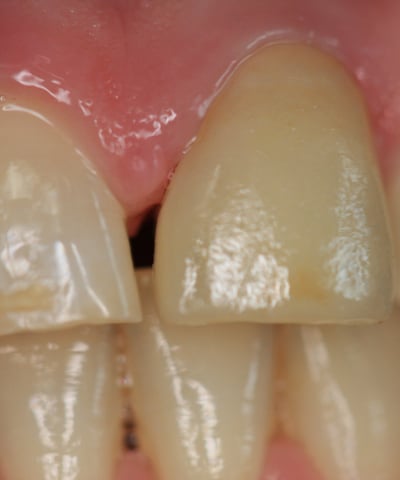

3. Preparazione del moncone e impronte:

Il moncone è stato preparato con una forma ideale per la ritenzione della nuova corona, e sono state prese le impronte digitali per la realizzazione della corona definitiva.

4. Prova estetica e inserimento della corona definitiva: